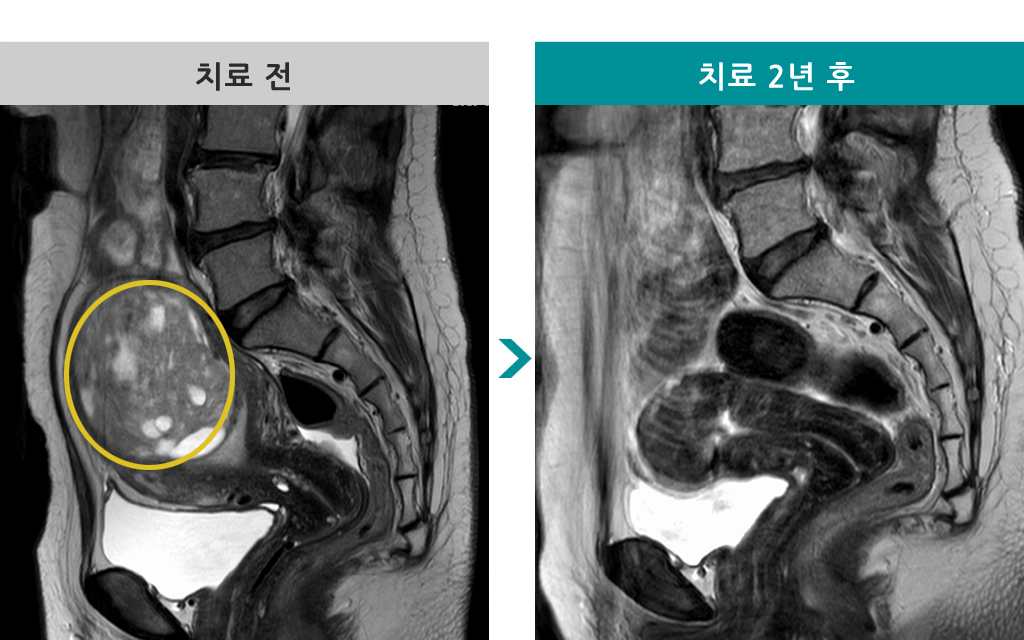

43세 [자궁선근증 색전술] 전후 MRI사진 비교